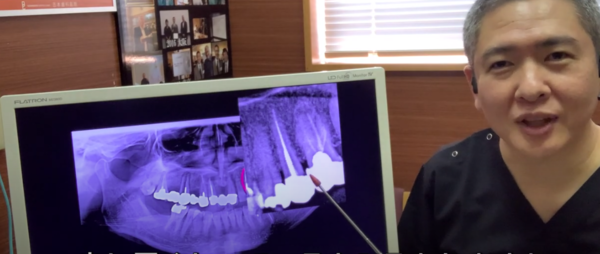

これをレントゲンで撮影するとどうなるのか?

実はこのように映ります。

レントゲンは硬いものが白く映ります。

根っこがあって

中に神経、血管

そして

代りにお薬が入っていますから

このお薬

芯棒

被せ物が

同一直線状にあります。

そして

根っこの周囲を

白いもので覆われています。

つまり

硬い骨で覆われている

ということですね。

この被せと根っこが

段差なく移行的になっている。

これ大事です。

少し黒くなっているところがありますね。

ここは硬いものがない

境い目のところがかたくない

つまり

虫歯になっている可能性がありますね。

レントゲンでは

膿んでいる

とか

腫れている

とかは

わからないんですね。

硬いものが

白く映るだけです

反対側です。

根っこがありません。

何らかの原因で

抜くことになったわけですけれども

残っている歯を繋いで

橋わたしをして

そして

ブリッジ治療をしたと

そうすると